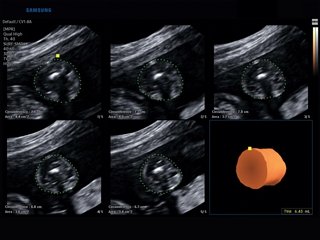

Atlas of ultrasound images (pg. 4)

The atlas of echograms is created for demonstrating the capabilities of Samsung Medison ultrasound scanners. The main part of ultrasound images is received from Korea, new echograms - from users of Samsung Medison scanners in Russia: institutes, diagnostic medical centres and private practicing doctors. The material is recommended for specialists of ultrasound diagnostics.